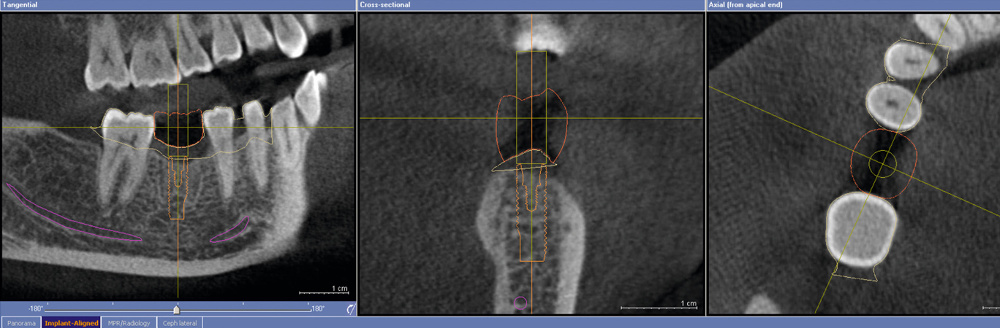

- Viene effettuato un esame radiologico, o TAC, per poter procedere alla ricostruzione in 3D dell’arcata interessata.

- L’esito dell’esame radiologico viene poi importato nel programma 3D per permettere al dentista di pianificare al computer l’intervento. Grazie a questo software, il dottore ha a disposizione una simulazione estremamente precisa, che gli consente di stabilire in anticipo la tipologia, la dimensione, il numero e i punti esatti in cui dovrà andare a posizionare gli impianti dentali.